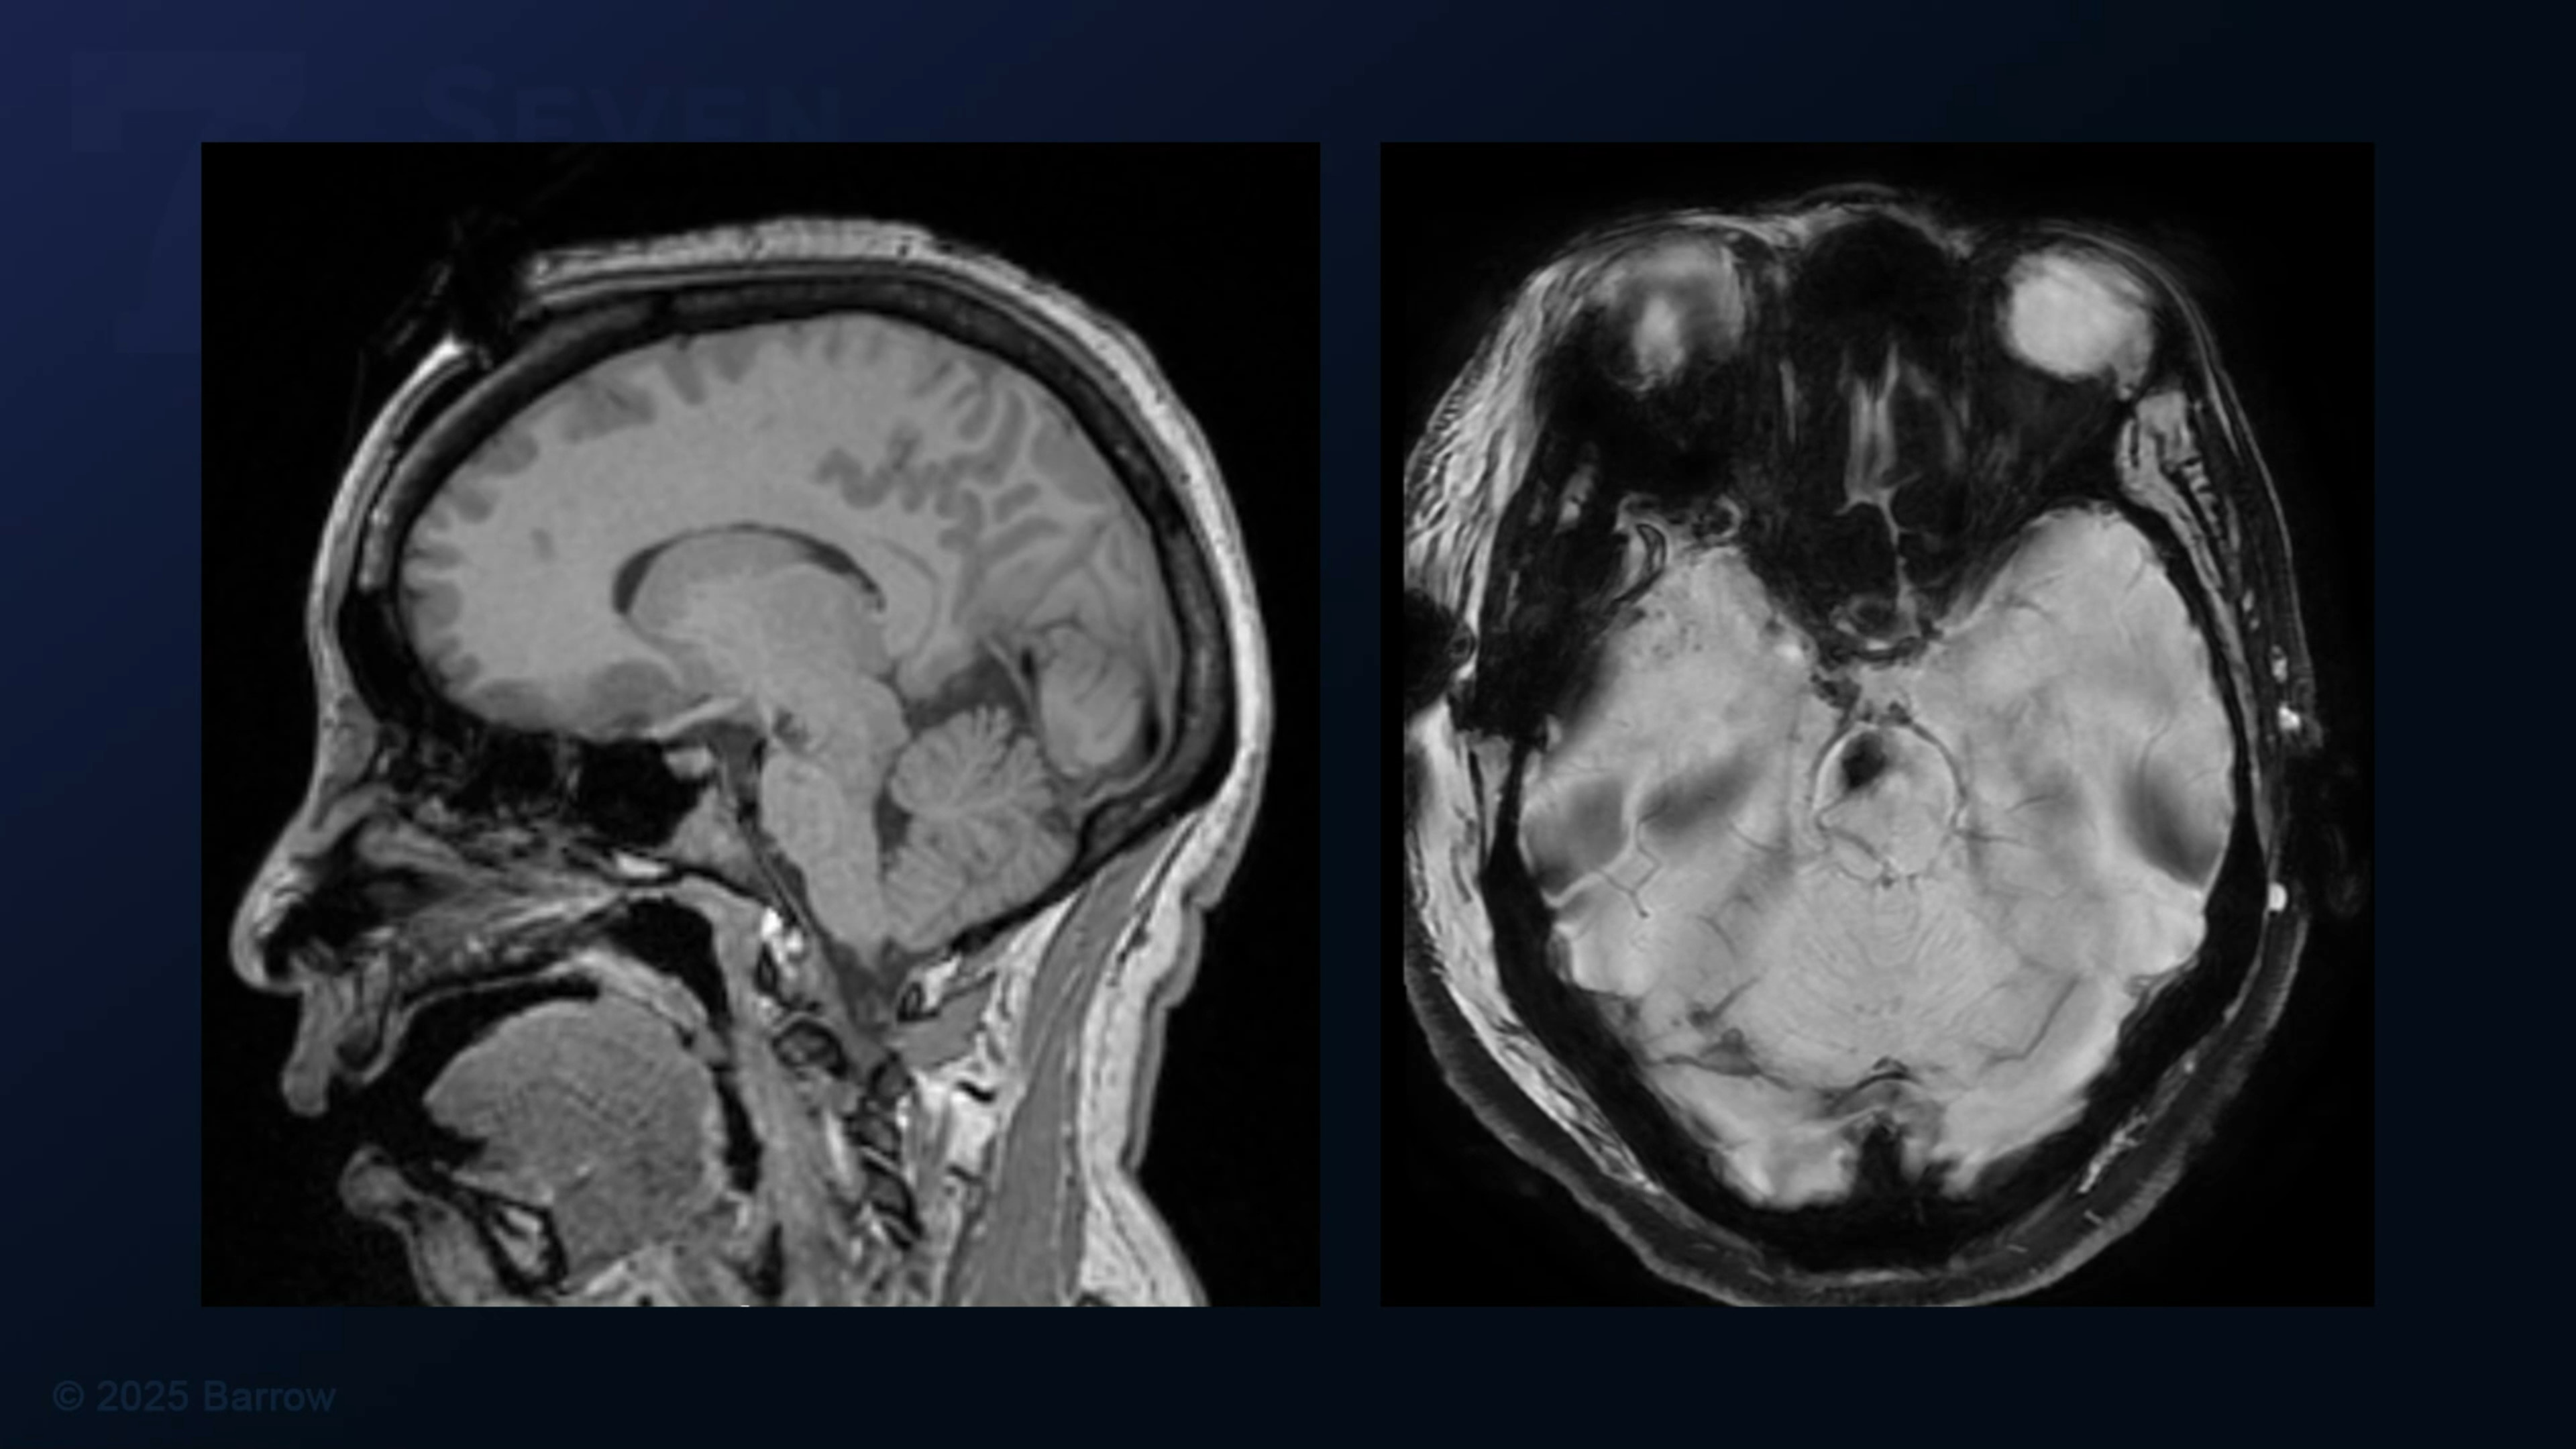

#486: Orbitozygomatic Craniotomy and Transsylvian-Transpeduncular Approach for Peduncular Midbrain Cavernous Malformation Resection

Episode 486 of Seven Series shows an orbitozygomatic craniotomy and transsylvian-transpeduncular approach for peduncular midbrain cavernous malformation resection.